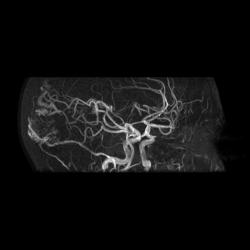

Артерио-венозная мальформация сосудов головного мозга.

3D TOF

При МР-ангиографии в режиме 3D TOF и 2D-TOF SPGR без применения контрастирующих веществ:

- определяется клубок расширенных и извитых патологических сосудов, получающих артериальную кровь из средней оболочечной артерии (ветвь наружной сонной артерии),  последняя расширена, из средней мозговой артерии и из задней мозговой артерии, эти артерии также шире, чем артерии контрлатеральной стороны. Дренирующие вены впадают в область стока синусов, а также в задний отдел верхнего сагиттального синуса

- дополнительно отмечены расширенные и извитые экстракраниальные сосуды, преимущественно под правой половиной задней черепной ямки.